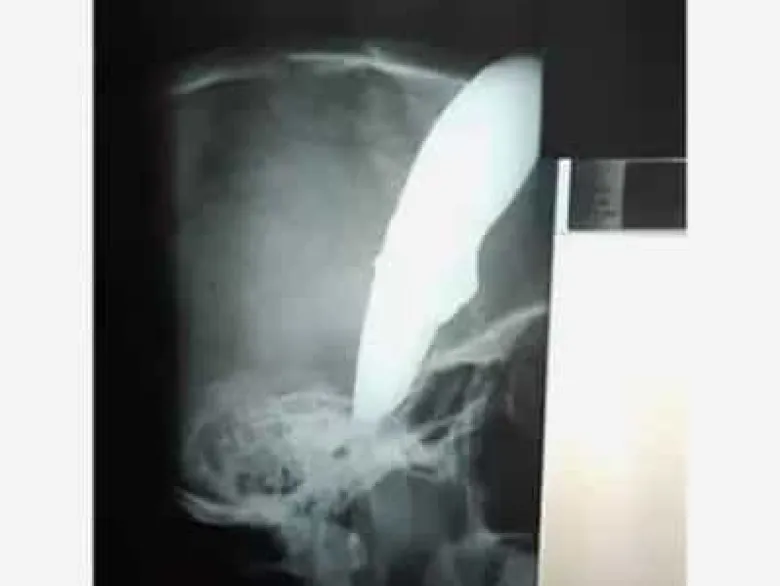

Դանակը գլխին հեծանվորդը ազատվելով հանցագործներից ինքն է գնացել բժիշկների մոտ

Քեյփթաունի բնակիչ Շոն Ուեյնը հարձակման է ենթարկվել եւ եկել է հիվանդանոց դանակը գլխին, հայտնում է Daily Mail պարբերականը։

Միջադեպը տեղի է ունեցել երկուշաբթի՝ նոյեմբերի 19-ին։ Տղամարդը հեծանիվով գնալիս է եղել սուշի ռեստորան աշխատանքի, երբ նրա վրա են հարձակվել երկու չարագործներ։ Նրանցից մեկը 34-ամյա Ուեյնի գլխին է հարվածել դանակով, իսկ 15 սանտիմետր սայրը մնացել է գանգի ներսում։ Հանցագործները փորձել են նրանից խլել հեծանիվը, բայց նրան հաջողվել է իրեն պաշտպանել, նրան ծեծել է եւ հեռացել։

Բժիշկների խոսքով՝ պացիենտի բախտը բերել է, որ սայրը չի մտել գանգը։ Ուեյնին անհապաղ վիրահատություն են արել, նրա վիճակը կայուն է։